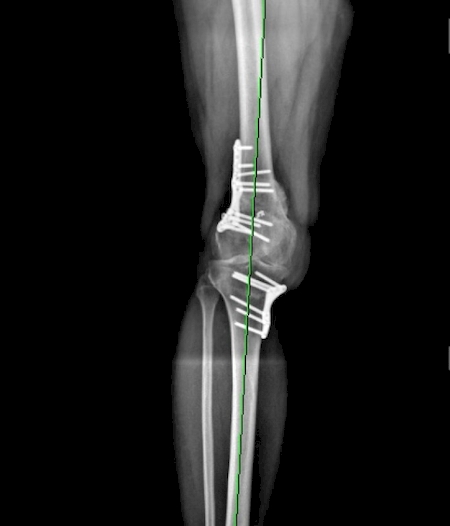

Ostéotomie Tibiale par fermeture externe pour genu Varum Ostéotomie Tibiale par fermeture externe pour genu Varum

Ostéotomie Tibiale par fermeture externe pour genu Varum

notre technique d'ostéotomie par fermeture externe à l'IML marseille pour traiter les patients avec les jambes (trop) arquées